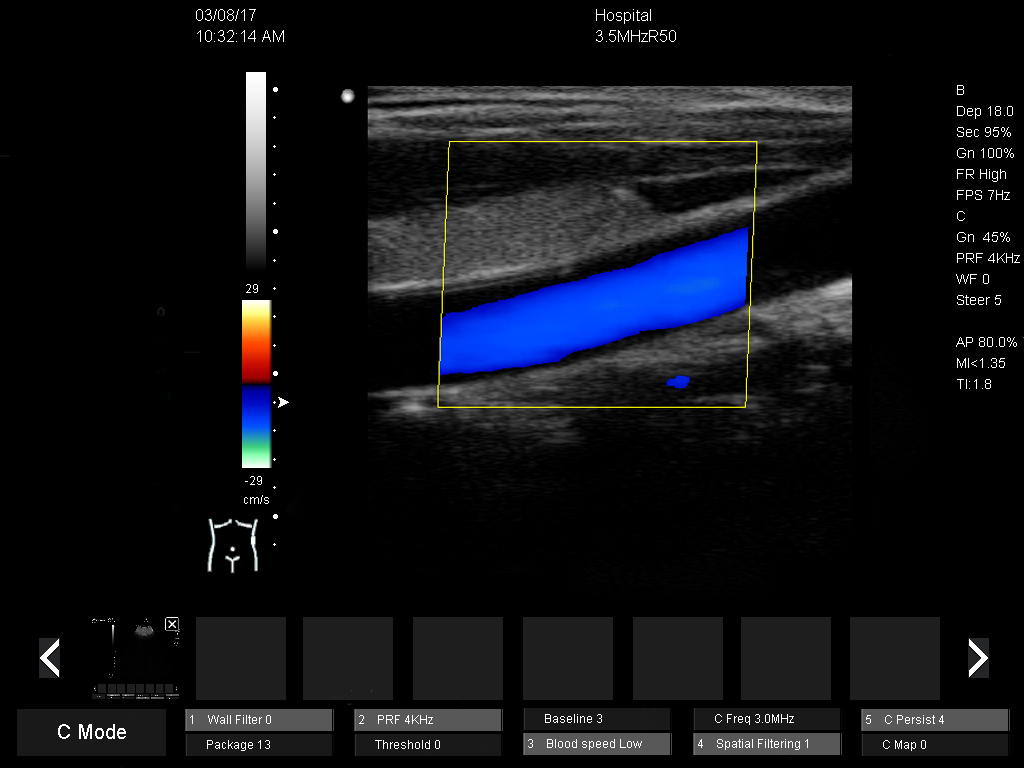

DMU51 Trolley Color Doppler Ultrasound Scanner Ultrasound Machine 3d/4d Color Doppler

6)Crystal clear 2D image and sensitive Color Doppler blood flow imaging system

1)Displaying mode:B,B/B,4B,B/M,M, B/C,B/C/D,B/D, duplex, triplex, CFM, PW,CW(optional), 4D(optional)

8)Vascular:Senosis D, senosis A, Intima, Arterial, Venous